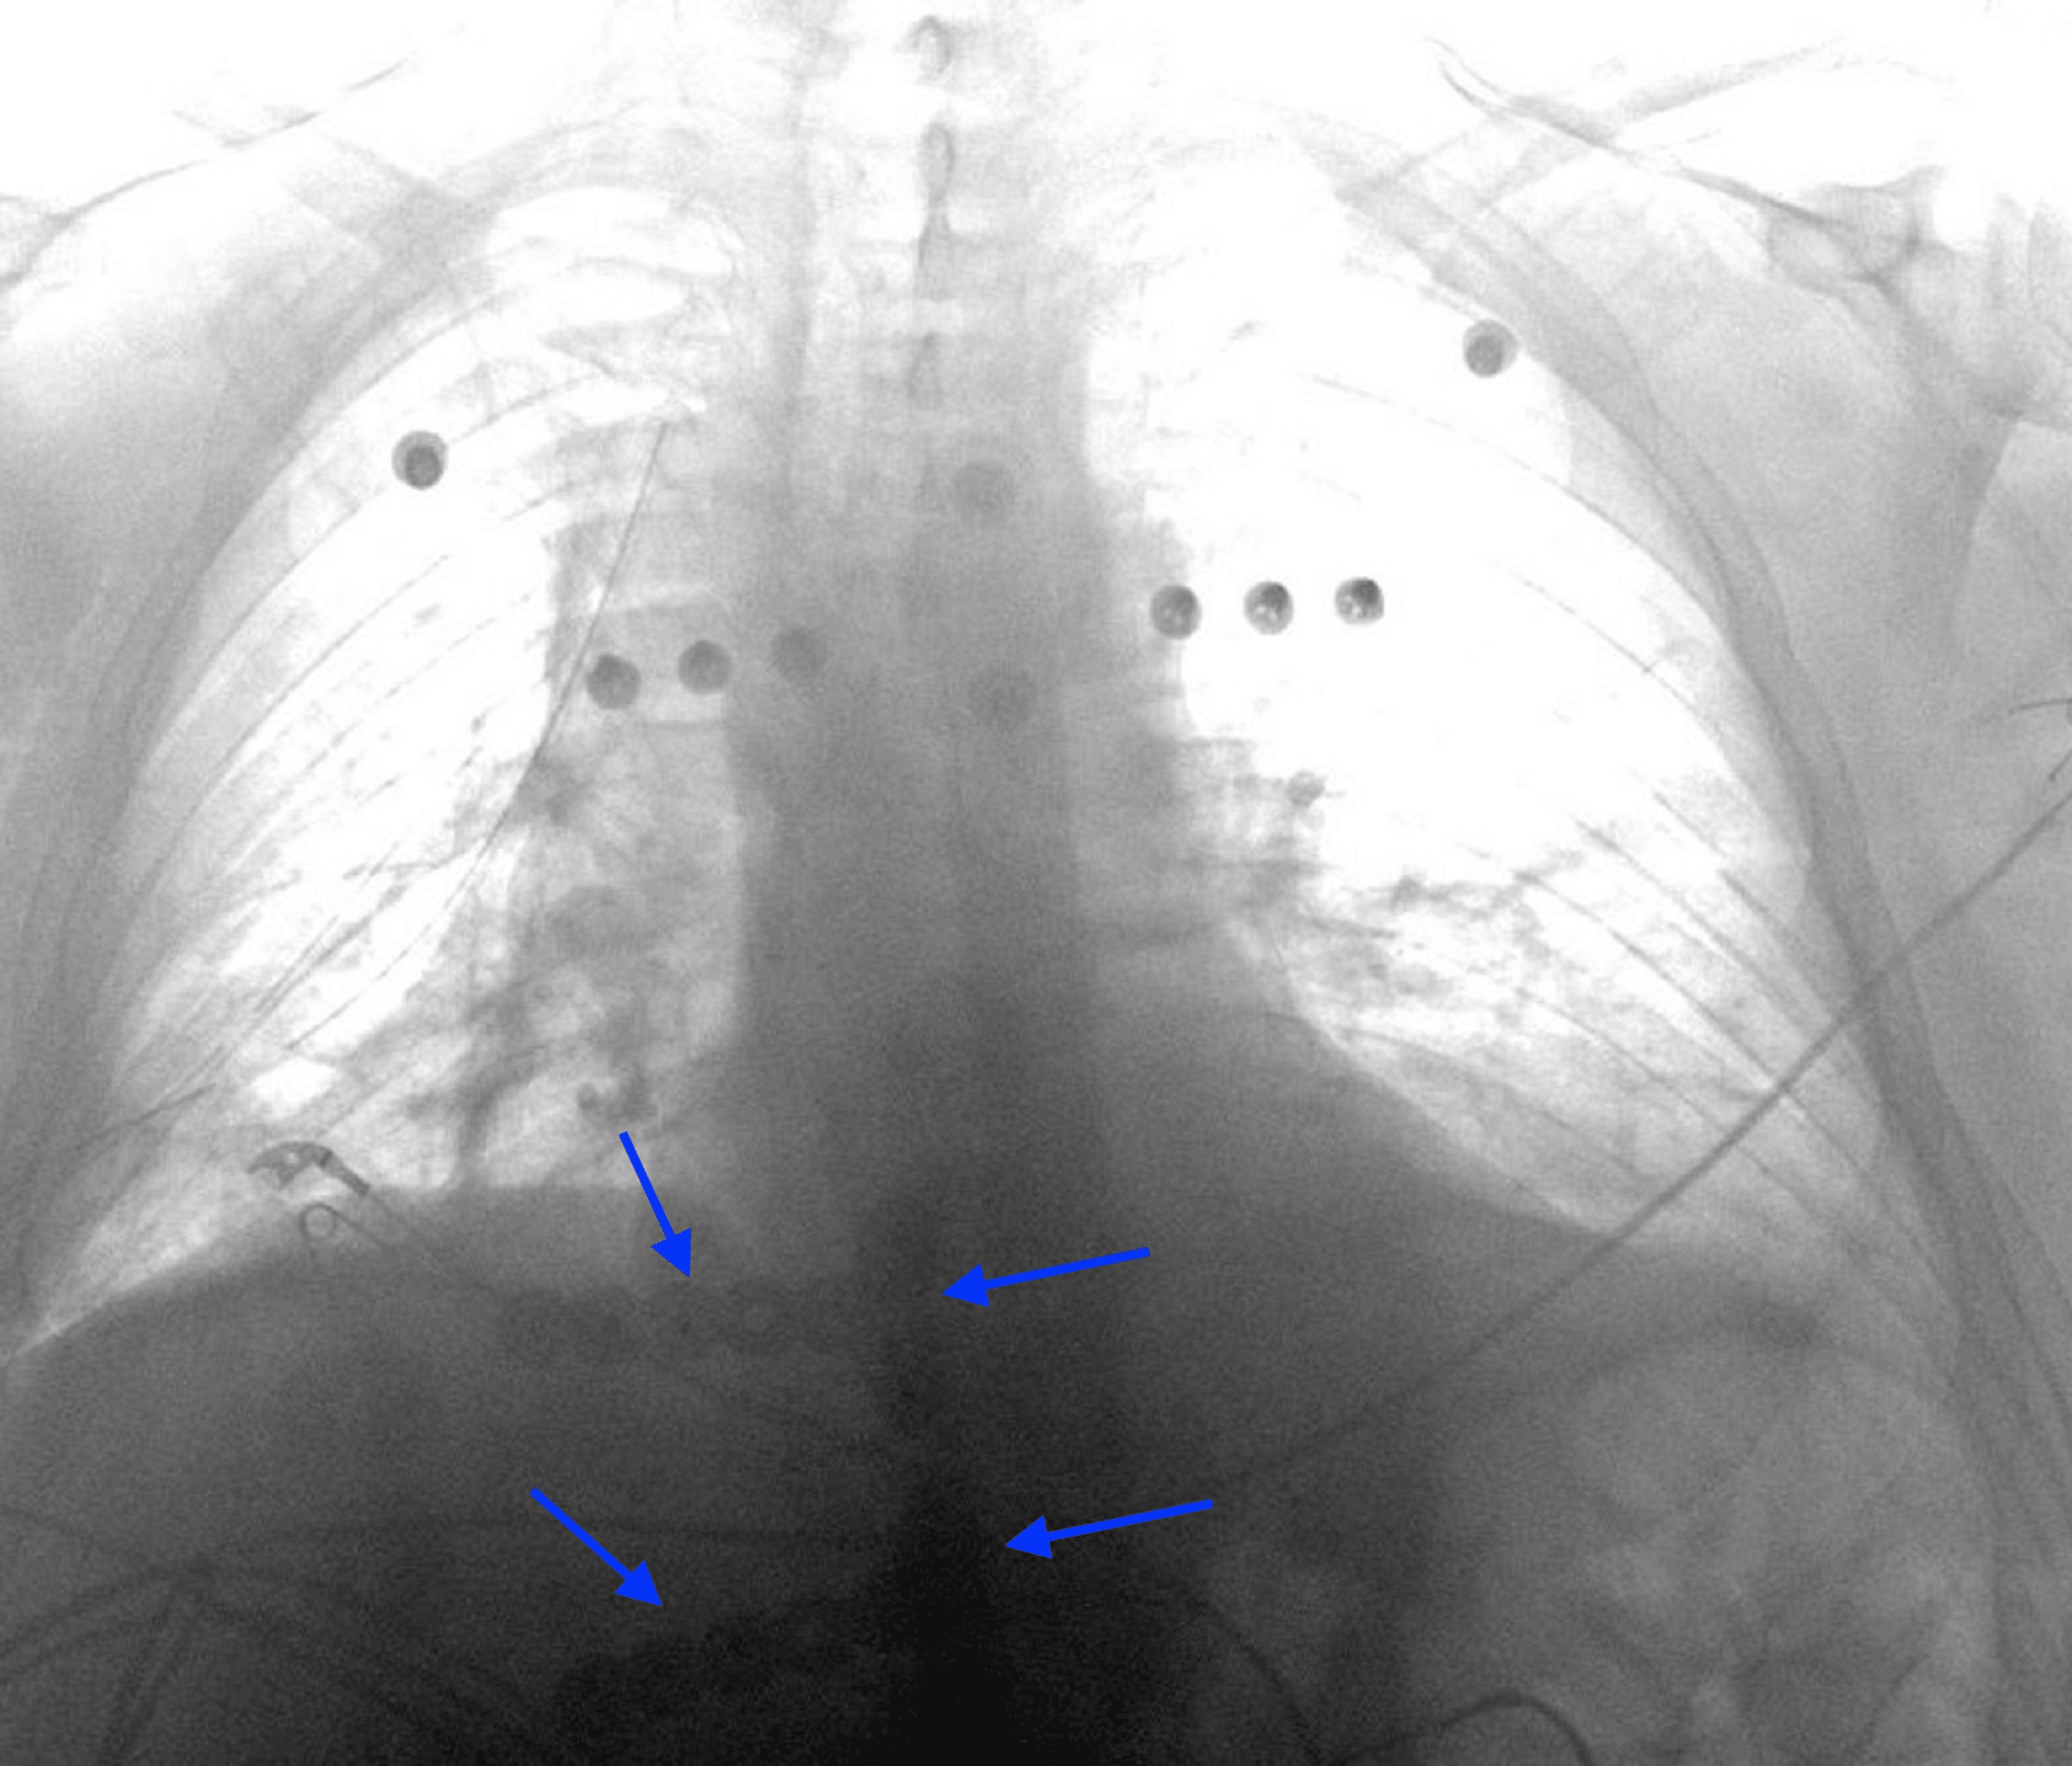

From www.researchgate.net

(b). Post operative chest Xray showing the titanium plate system. Download Scientific Diagram Titanium Plate In Chest the sternal fixation system consists of titanium locking plates that function with 3.0 mm titanium locking screws, similar to those used in the mandible. bilateral sternoclavicular joints were accumulated in the manubrium. two recent studies suggest that titanium plate fixation can provide a primary method for sternotomy closure in patients at risk. there is increasing evidence. Titanium Plate In Chest.